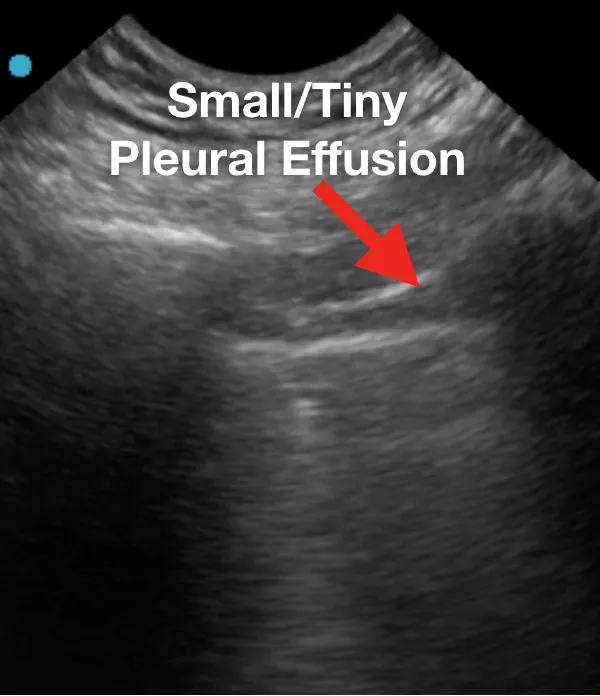

Ниже представлен ряд изображений патологических изменений, которые Вы можете увидеть при УЗИ легких пациентов с COVID-19. Эти изменения можно найти в любой части легкого, поскольку COVID-19 имеет мультифокальное распределение. Возможно сочетание областей нормального легкого и области с патологией. Патологические изменения легких могут отсутствовать в начале заболевания и при легком течении COVID-19, однако, по мере его прогрессирования, Вы можете наблюдать всё больше патологических изменений.

Ниже приведены примеры УЗ-картины легких пациентов с COVID-19.